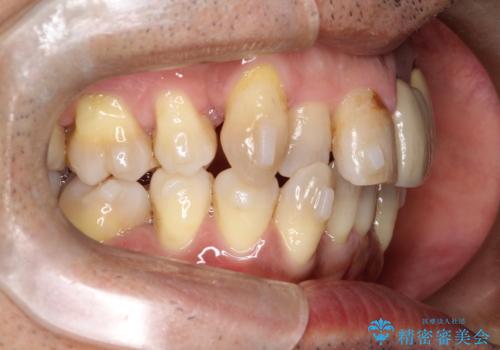

- 50代の患者様で、右上の八重歯と歯並びの乱れを気にされてご来院されました。特に、すでに装着されている前歯のセラミックブリッジを外したくないという強いご希望がありました。精密な検査の結果、八重歯を治すためのスペースが不足しているため、右上の4番目の歯(小臼歯)を抜歯し、そのスペースを利用して歯並び全体を整える治療計画を立案。装置には目立たないインビザラインを採用し、ブリッジを温存しながら八重歯の改善を目指しました。

今回の治療で最も重要だったのは、患者様のご要望通り既存のセラミックブリッジを外さずに矯正を進める点でした。計画通り右上の小臼歯を抜歯し、透明なインビザラインを使用して抜歯スペースを閉じながら、八重歯を正しい位置へ移動させました。ブリッジの形態と調和するに、他の歯の移動を工夫をすることで、複雑な条件をクリア。治療の結果、長年気にされていた八重歯が解消され、見た目が大きく改善しました。50代からでも、ご自身の要望を叶えながら、美しく機能的な歯並びを獲得していただけました。